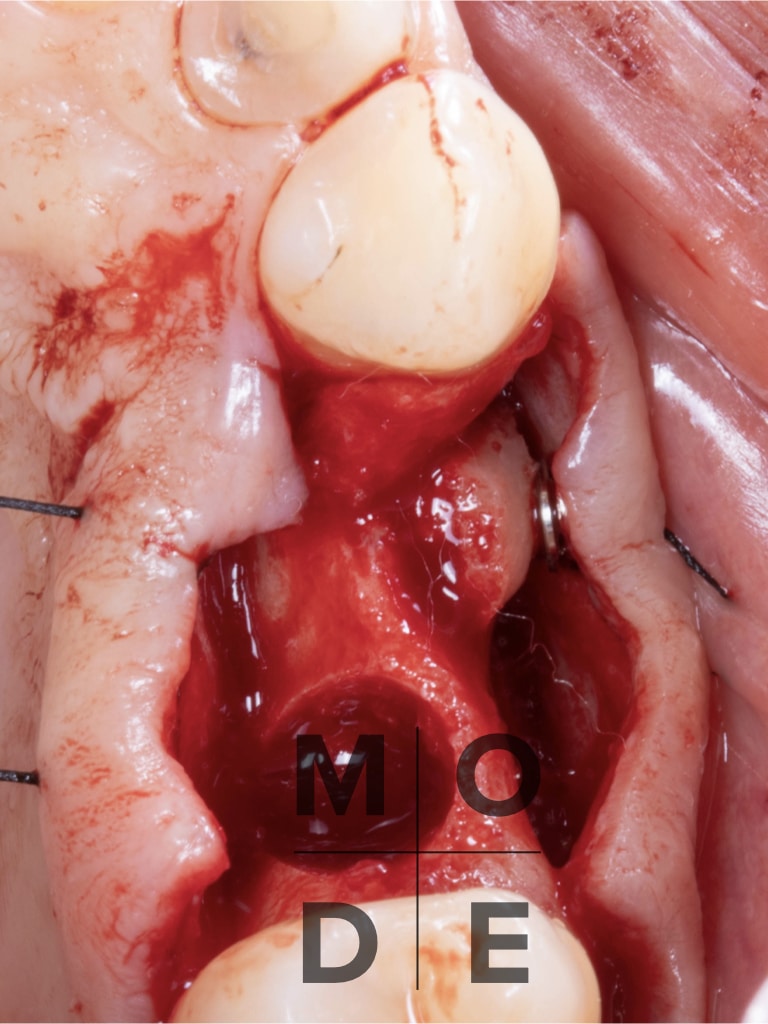

Follow Up at 4 months

Implants placement